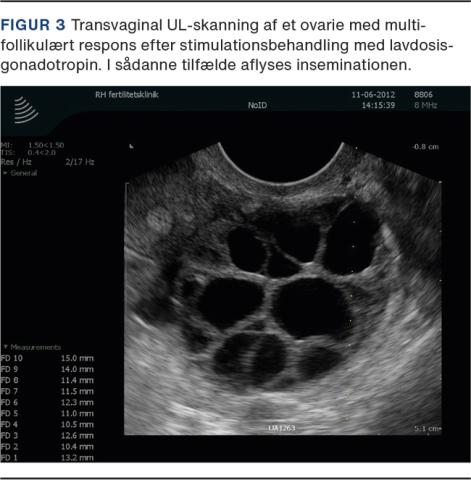

Målet med den medicinske behandling af anovulatorisk infertilitet er at opnå udvikling og ovulation af en enkelt moden follikel (monoovulation) (Figur 2) ved indirekte eller direkte stimulation af ovarierne efterfulgt af timet coitus eller insemination [11].

Ved direkte stimulation af ovarierne anvendes injektionsbehandling med gonadotropiner [14]. Behandlingen kan være en klinisk udfordring pga. den øgede risiko for hyperrespons hos kvinder med PCOS (Figur 3), og follikeludviklingen skal monitoreres tæt. Der gives en lav dosis gonadotropin fra cyklusdag 2-5, og kvinden ses til kontrol efter ca. syv dage og derefter ved behov, indtil der ses modning af en enkelt follikel. Ved amenoré og smalt endometrium kan stimulationsbehandlingen påbegyndes på en vilkårlig dag. Når der ses en follikel på 17 mm i diameter, induceres ovulation med hCG. Ved udvikling af to modne follikler bør patienten informeres om risikoen for flerfoldsgraviditet ved IUI. Ved udvikling af tre follikler ≥ 14 mm i diameter kan behandlingen overvejes aflyst eller konverteret til in vitro-fertilisering (IVF). Ved udvikling af mere end tre follikler ≥ 14 mm i diameter skal cyklus aflyses eller konverteres til IVF. Kvinder med PCOS-relateret infertilitet har generelt gode chancer for at opnå graviditet, når en ovulatorisk cyklus er etableret [15]. Der er rapporteret om kumulative graviditetsrater på op til 78% og en samtidig lav forekomst af flerfoldsgraviditeter (< 3%) og hyperrespons efter ovulationsinduktion med lavdosisgonadotropinstimulation [16].